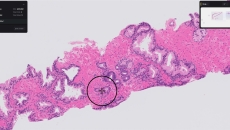

Paige Prostate analyzes digitized biopsy slides and identifies areas that could be cancerous for the pathologist to review further.